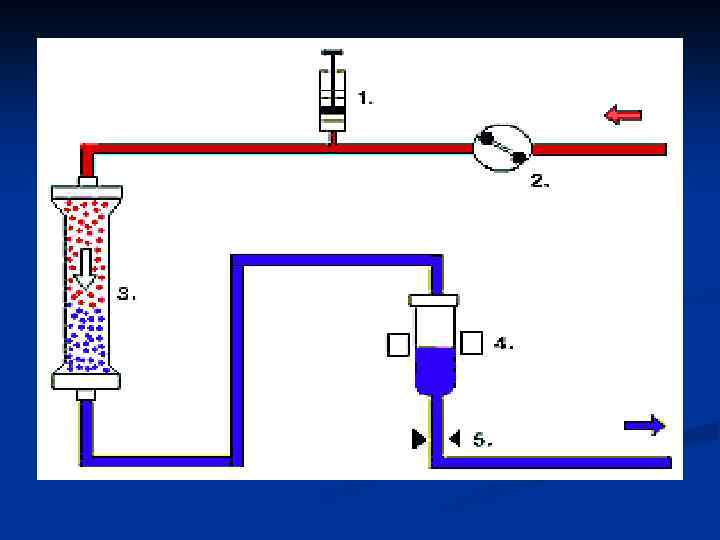

n Гемосорбцияны қандағы әр түрлі зиянды заттардан тазарту үшін қолданады. Ағзада әдетте бұл бауырдың жұмысы. «Гемо» -қан, «сорбция» -ағзаны уландырушы зиянды заттардан тазарту, яғни қанды, қан сары суын, лимфаны токсиндерден, улы заттардан тазарту үшін сорбентпен толтырылған арнаулы түтік арқылы сүзгіден өткізілуі.